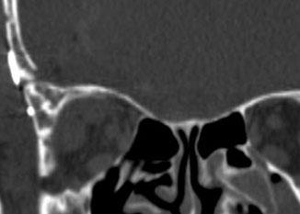

Ⅱ 60歳代男性

外眼筋四角錐内悪性リンパ腫

右視力・視野障害、眼球突出を主訴として来院した。摘出手術後視機能は改善し、眼球突出は消失した。骨条件術後CTでは、眼窩壁が整復され術前と同じ形状を維持していることがわかる。

術後 骨CT